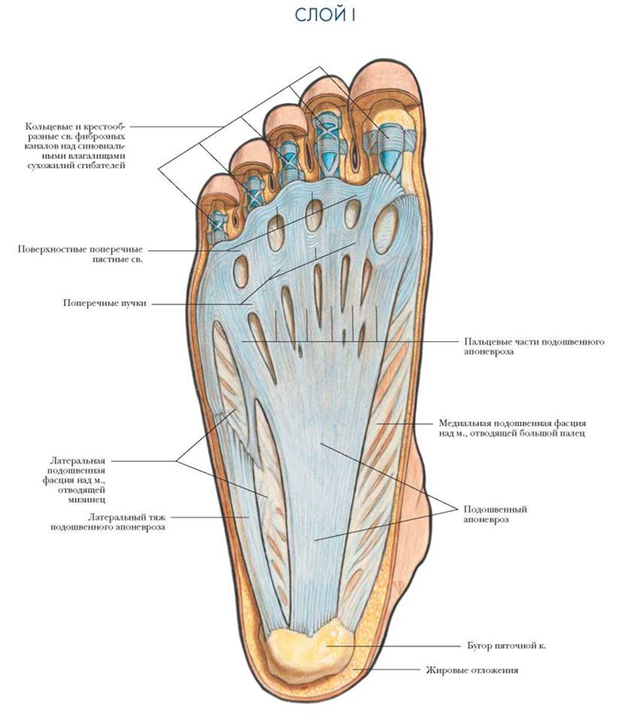

По низу стопы от пятки к головкам плюсневых костей и основным фалангам идет толстая широкая жила, которая называется подошвенной, или плантарной, фасцией. Эта фасция отмечает за пассивную стабилизацию продольного свода – той ямки на стопе, в которую в кроссовке упирается супинатор. Стабилизация фасцией похожа на тетиву лука.

Свод держится за счет разницы в длине дуги продольного свода и длины фасции (фасция короче и поэтому выгибает продольный свод). Это очень упрощенная модель, не учитывающая другие связки стопы, мышцы, а также наличия в стопе суставов и костей разного размера и формы, но для понимания происхождения плантарного фасцита/пяточной шпоры эта модель достаточна.